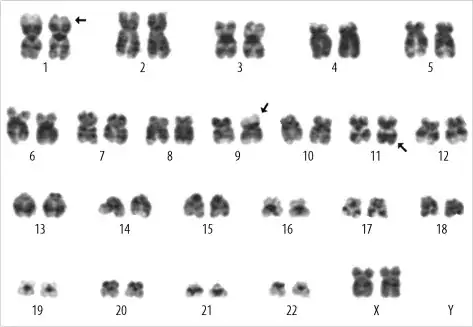

Many species (including humans) have two sets of each chromosome. If you add the other chromosome in the picture, you would see a pair of chromosome. One chromosome of the pair is said to be homologous to the other one. Below is a cladogram during the metaphase of a human (I let you figure out the sex) showing each pair of chromosome.

There are 23 pairs of chromosomes, that is 46 chromosomes. Your picture shows only one chromosome per pair, that is your picture shows only 23 chromosomes. In other words, your picture shows the haploid genome and not the diploid genome.